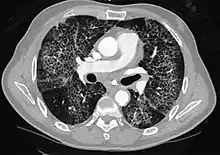

CT image showing patchy areas of ground-glass opacities representing pulmonary edema.

The diffuse pattern typically refers to GGOs in multiple lobes of one or both lungs. Broadly, a diffuse pattern of GGO can be caused by displacement of air with fluid, inflammatory debris, or fibrosis. Cardiogenic pulmonary edema and ARDS are common causes of a fluid-filled lung. Diffuse alveolar hemorrhage is a rarer cause of diffuse GGO seen in some types of vasculitis, autoimmune conditions, and bleeding disorders.[6]